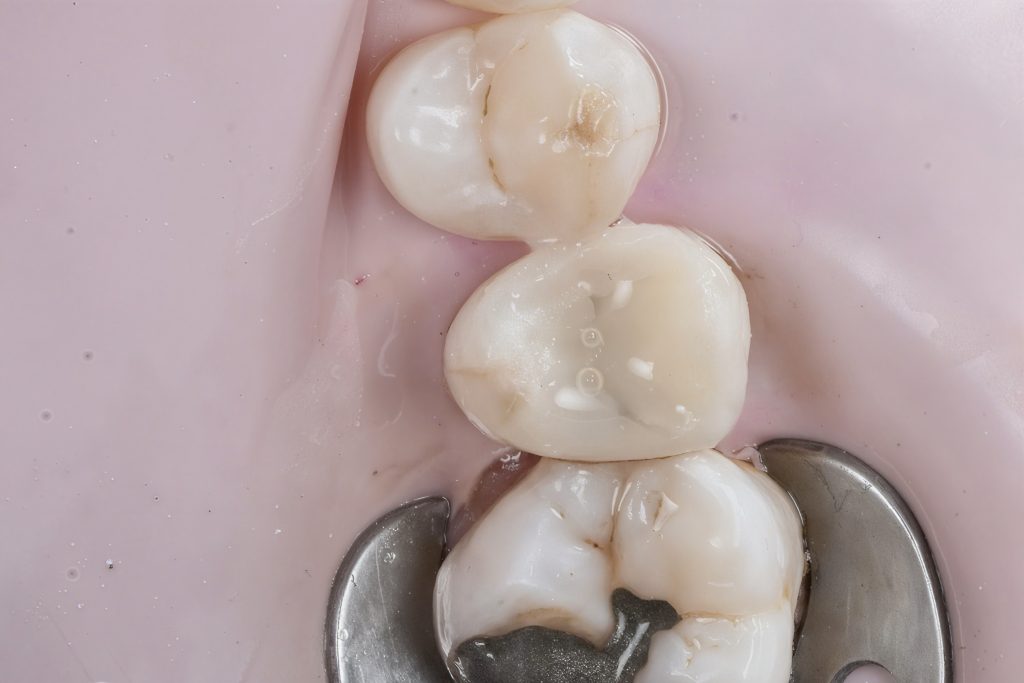

6. Finishing and Polishing

Proximal finishing strips, flame burs and Sof-Lex spiral wheels were used. Final gloss achieved using Lucida Diamond Polish (Fig 9–10).

Outcome

- Tight, stable proximal contact restored

- Gingival health preserved

- Seamless integration with natural tooth structure

- Functional and aesthetic stability achieved

- Patient satisfied and symptom-free

- Final occlusal view

- Restored proximal integrity and anatomy